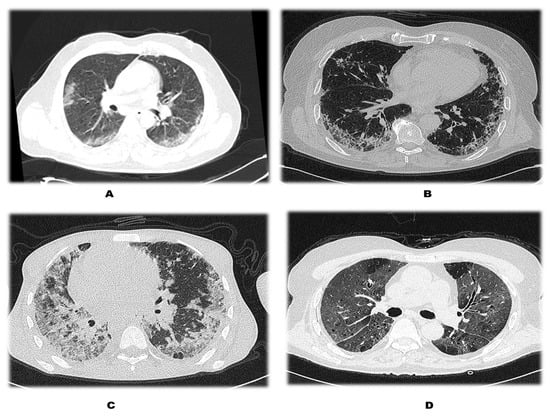

| CLASS | CTSS (out of 25) |

| MILD | 0–11 |

| MODERATE | 12–18 |

| SEVERE | >18 |

| CT Severity Score | Patients without DM (n = 115) | Patients with DM (n = 37) | Total | p Value |

|---|---|---|---|---|

| 0–11 {Mild} | 65 (56.52%) | 12 (32.43%) | 77 (50.66%) | 0.024 |

| 12–18 {Moderate} | 46 (40%) | 22 (59.46%) | 68 (44.74%) | |

| >18 {Severe} | 4 (3.48%) | 3 (8.11%) | 7 (4.61%) | |

| Total | 115 (100%) | 37 (100%) | 152 (100%) |